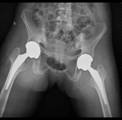

常规开展膝、髋、肩、肘关节置换及翻修手术,并开展单髁置换、胫骨高位截骨术等。治疗各类关节创伤及疾病,如股骨头缺血坏死,膝关节老年性骨性关节炎、类风湿关节炎,股骨颈骨折,股骨转子间骨折。

双侧强直髋术前/术后